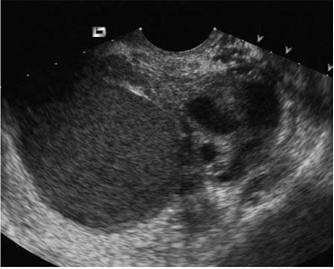

Nang lạc nội mạc tử cung có hình ảnh một khối u echo kém, thành trơn láng, chứa dịch dạng vân mây. Những nang lạc nội mạc tử cung mới thành lập có dạng hình cầu, thành nang tương đối trơn láng. Những nang được thành lập lâu, dần dần hình dạng thay đổi, thành nang có thể có góc cạnh do phúc mạc bị dính, co kéo, thành nang trở nên dày, echo đặc [7].

Hình 0. Hình ảnh siêu âm nang lạc nội mạc tử cung ở buồng trứng. Nguồn: tài liệu tham khảo số [Error! Reference source not found.]

Siêu âm hai chiều cho thấy nang lạc nội mạc tử cung có thành dày, chứa dịch đồng nhất, echo kém, dạng vân mây.